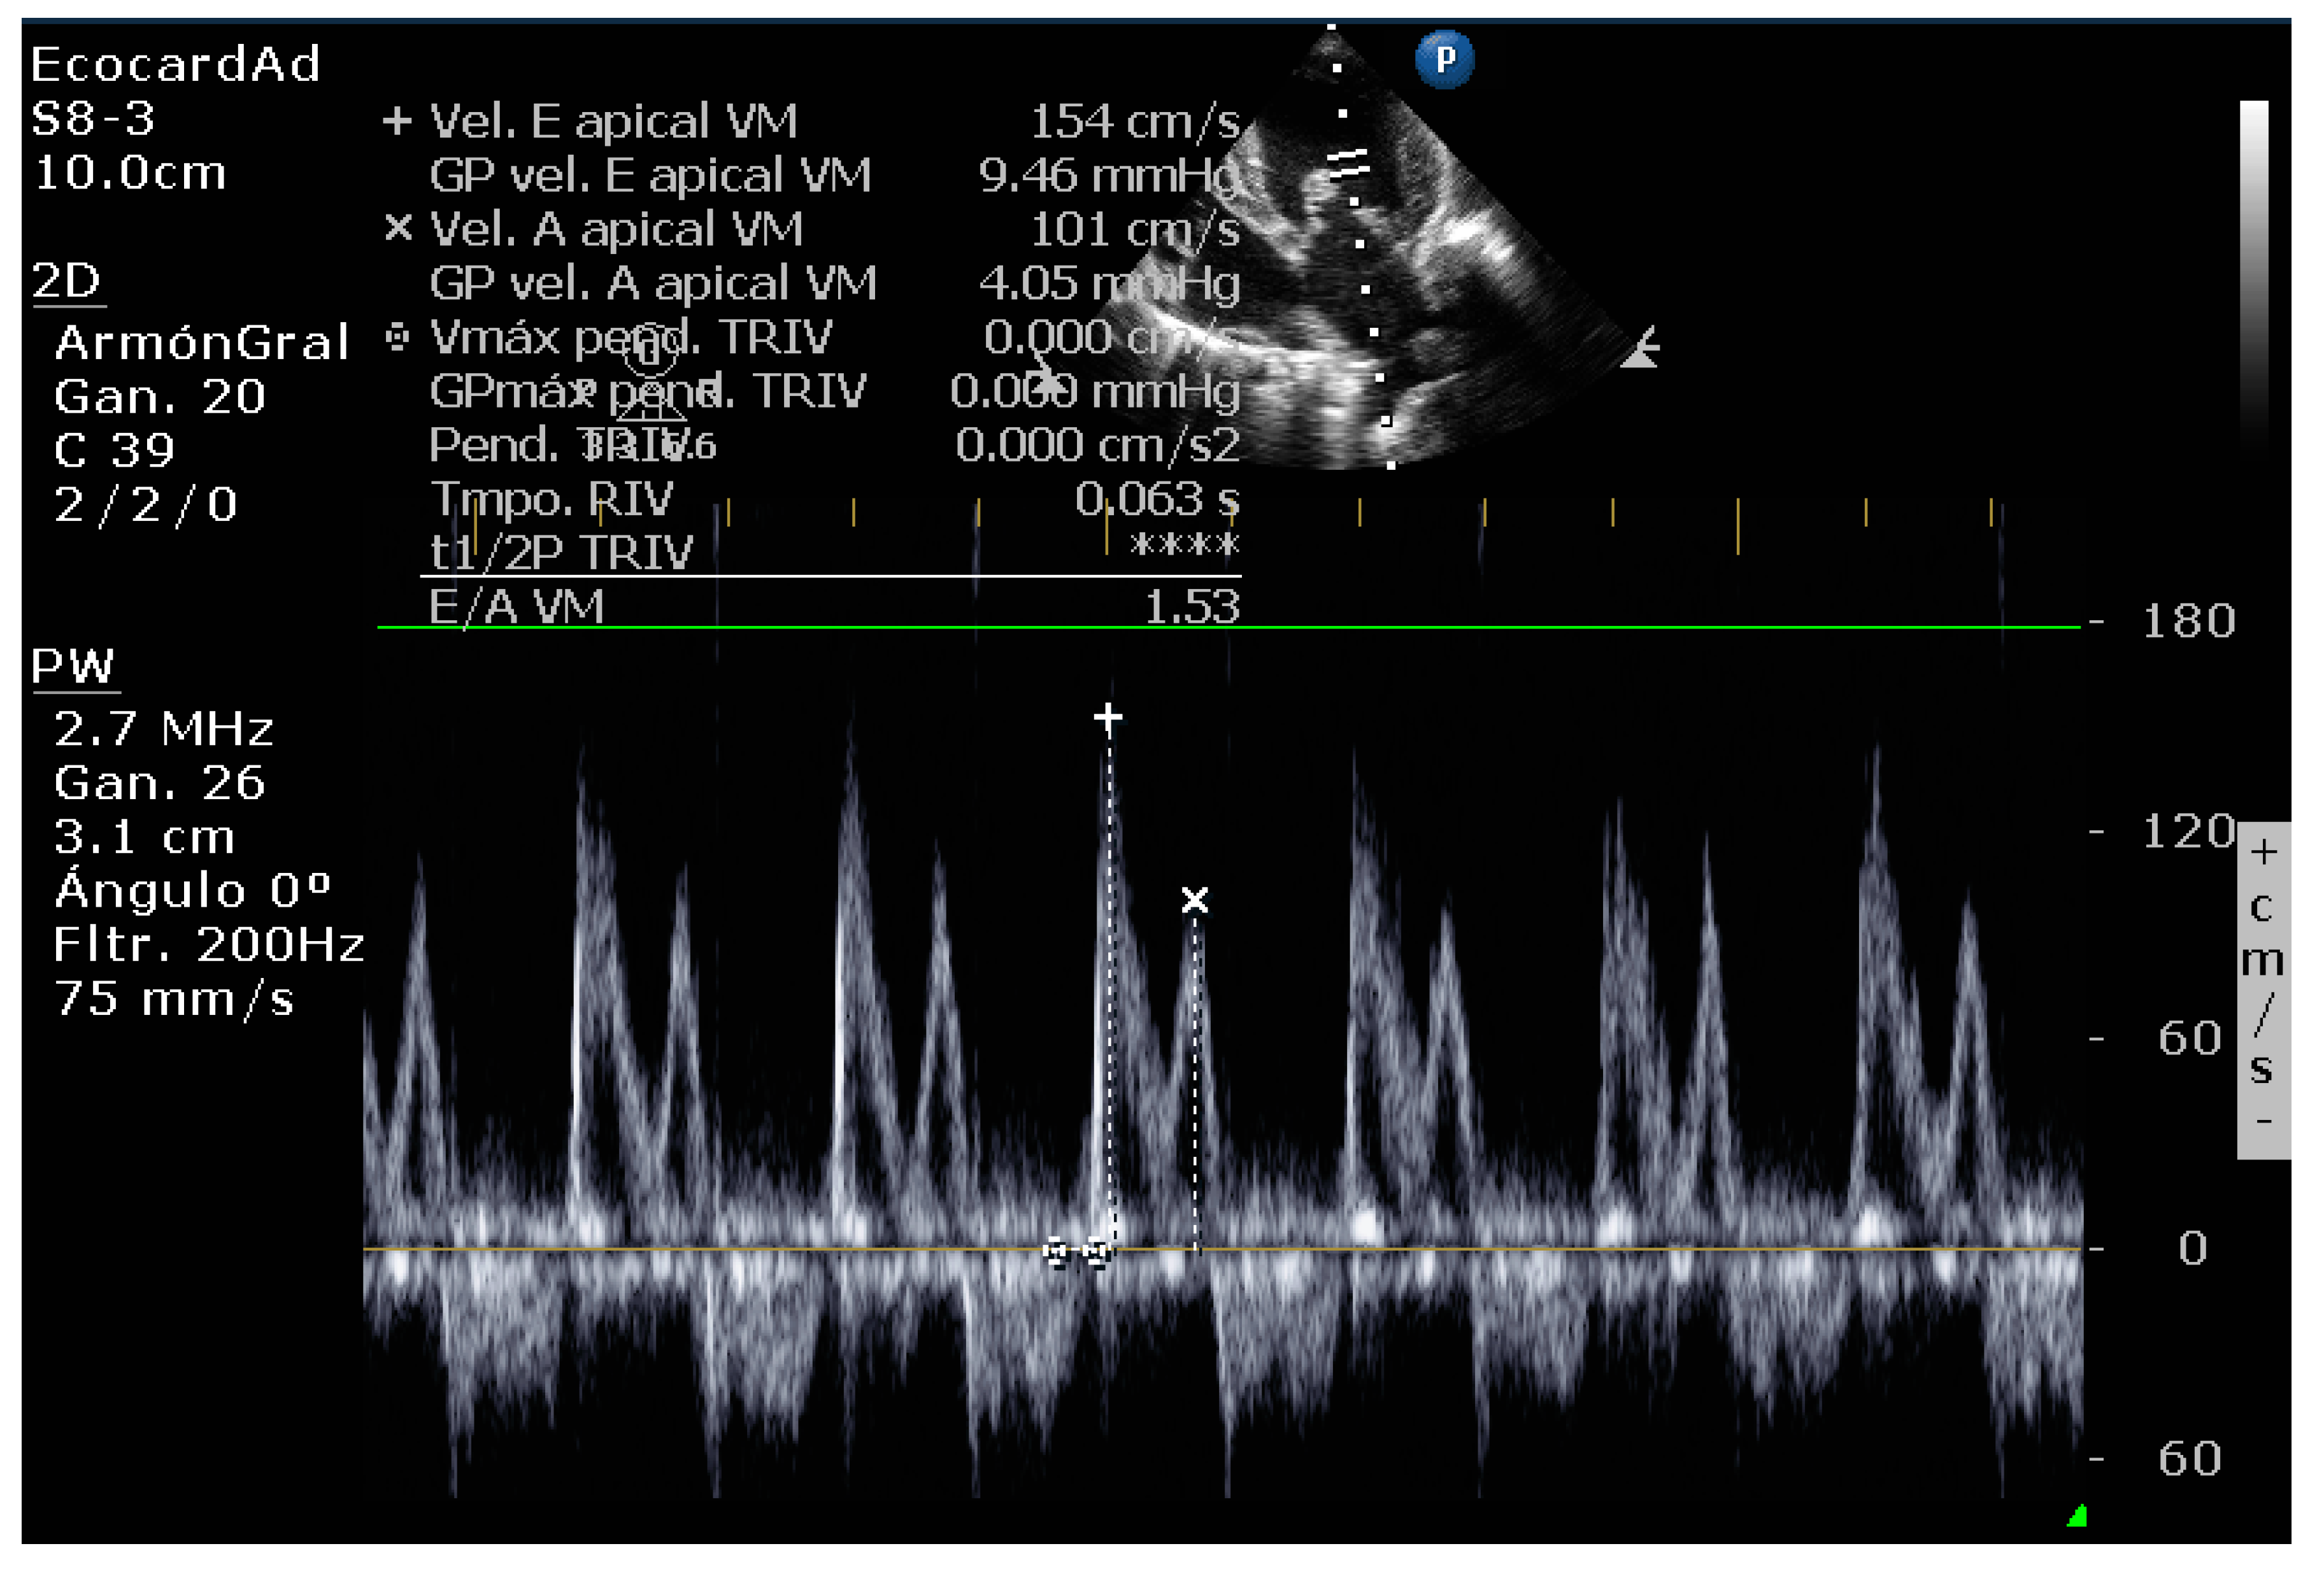

4.8.5. Vmax Wave E

4.8.6. E-Wave Deceleration Time

4.8.7. E/IVRT Ratio

4.8.8. E/é Ratio of the Mitral Annulus